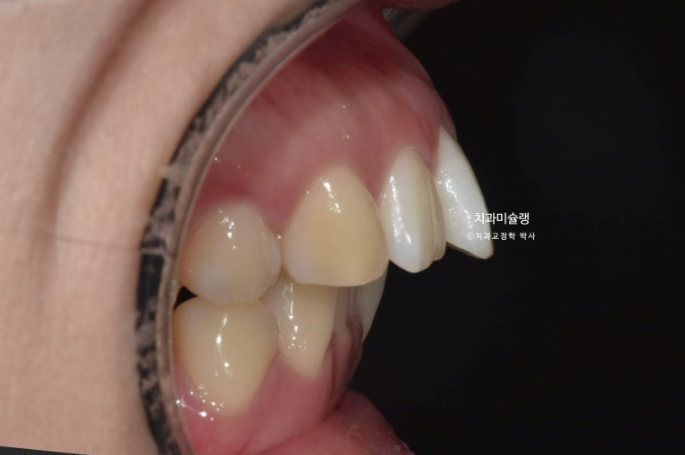

윗니 돌출이 심합니다.

아랫니 기준으로 약 1센치가 더 튀어나와 있습니다.

골격분석 결과 심한 상악골 전방 돌출을 동반한 골격성 2급 부정교합 입니다.

상악과 하악의 골격 부조화가 심해 아래턱이 상대적으로 뒤로 밀려있는 상태여서 위 앞니 각도를 이상적으로 유지하기가 쉽지 않습니다.